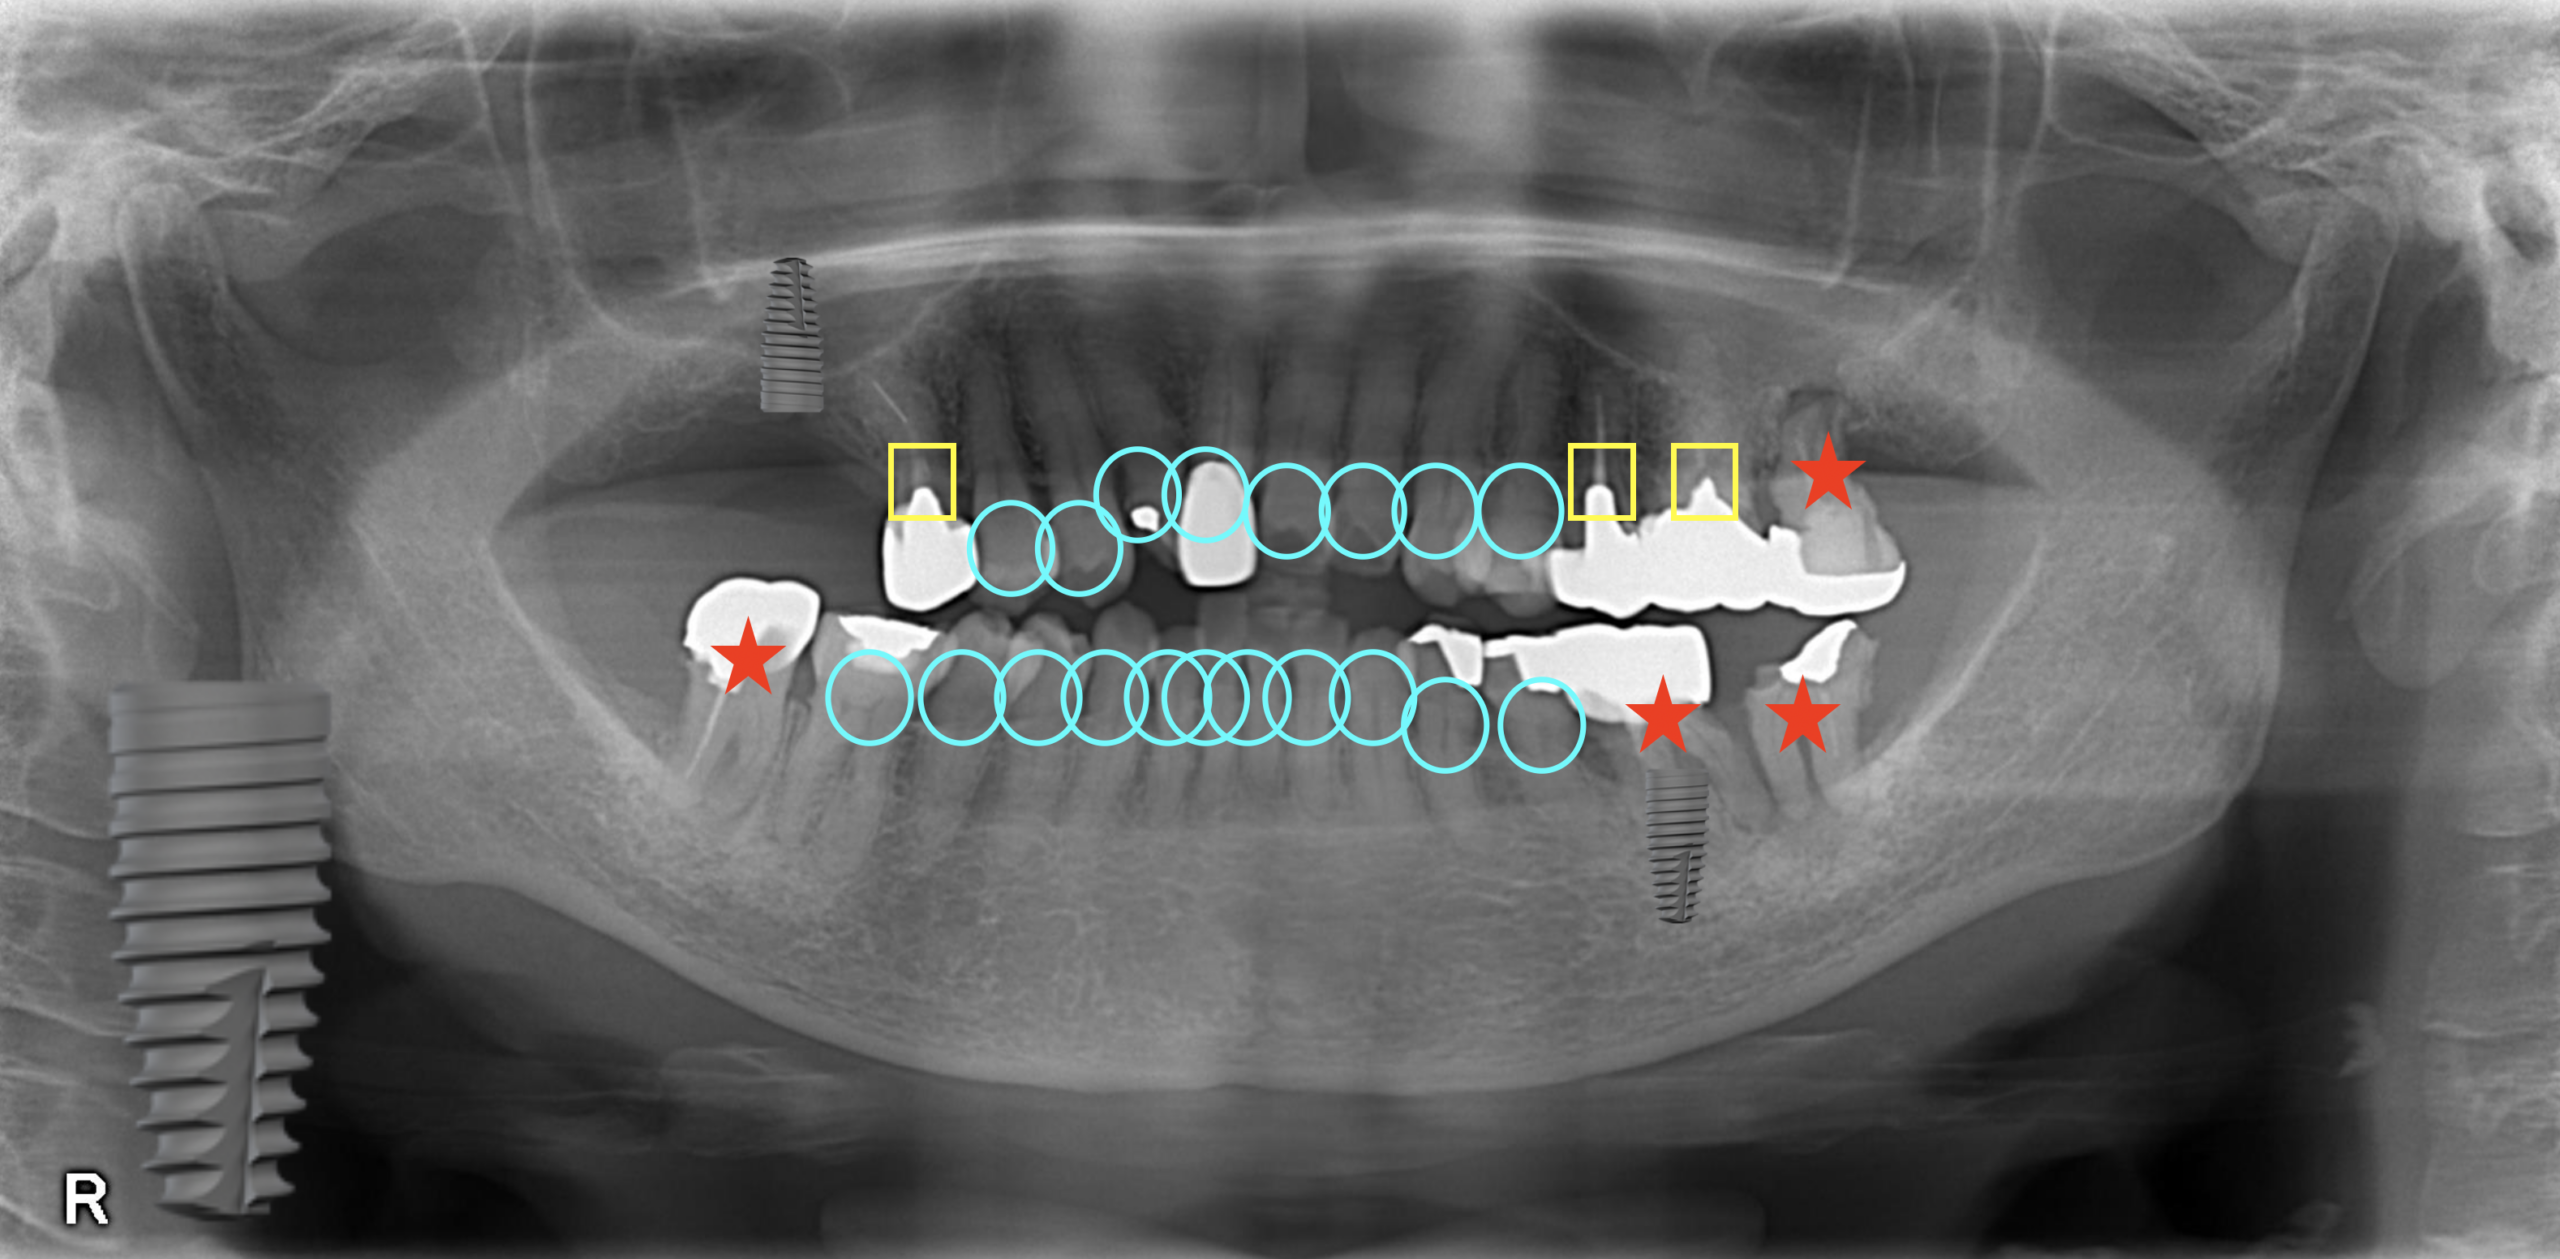

⁂左上

向かって左上のインプラント治療は、第1大臼歯までを補うという意味合いから必要だと考えます。

左上のインプラントの歯は、左下の奥から2番目の青い丸の歯と噛むことになります。

⁂左下

左下の赤い星の歯は、第2大臼歯であること、また噛む歯がないため、抜歯することになります。

⁂右下

一番右下の赤い星の歯(第2大臼歯)は、骨がないことから抜歯することになります。

右下の右から2番目の赤い星の歯(第1大臼歯)は、今治療して仮に治ったとしても10年後、20年後にちゃんと歯として成立している確率は低いこと、また10年後には70代になっていて、70代になってから再治療になるのはおそらく難しい、という判断から抜歯することになります。

第1大臼歯は咀嚼にも重要な歯なので補うことを考えないといけません、この部位にはインプラント治療が必要でしょう。

⁂右上

右上の赤い星の歯(第2大臼歯)は、骨がないこと、根尖病変が小さくはないこと、虫歯があること、噛み合わせが不利なこと、噛む歯がないことから、抜歯判断になります。

つまり、治療開始時点で4本の抜歯、2本のインプラント治療が必要です。

4本も抜くの・・・?と思われる方が多いでしょう。もちろん歯は多いことにこしたことはありません、しかし年齢や治療介入のタイミング、噛み合わせ、今後の人生でトラブルが少ないように、ということを考え合わせると、今回は第2大臼歯を積極的に補うことはしないほうが得策だと判断します。

さらに、黄色の四角の歯は今後30年もつかどうかわからない歯です。

黄色の歯が最後までもってくれたらいいけれど、もしかしたら、

最終的にインプラント治療が5本必要になる可能性があるわけです。